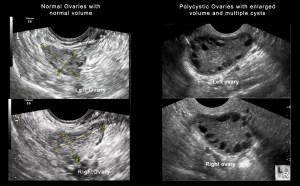

Usually, a single ovum is formed during one cycle. However, in the case of PCOS, several follicles mature and remain in the ovaries at a given time, giving rise to the observation of a ‘polycystic’ appearance of the ovaries in ultrasound scans. This condition may give rise to anovulatory or irregular cycles.

Image from Mayo Clinic

- an ultrasound scan to observe the presence of multiple follicles, which appear as cysts, in slightly enlarged ovaries